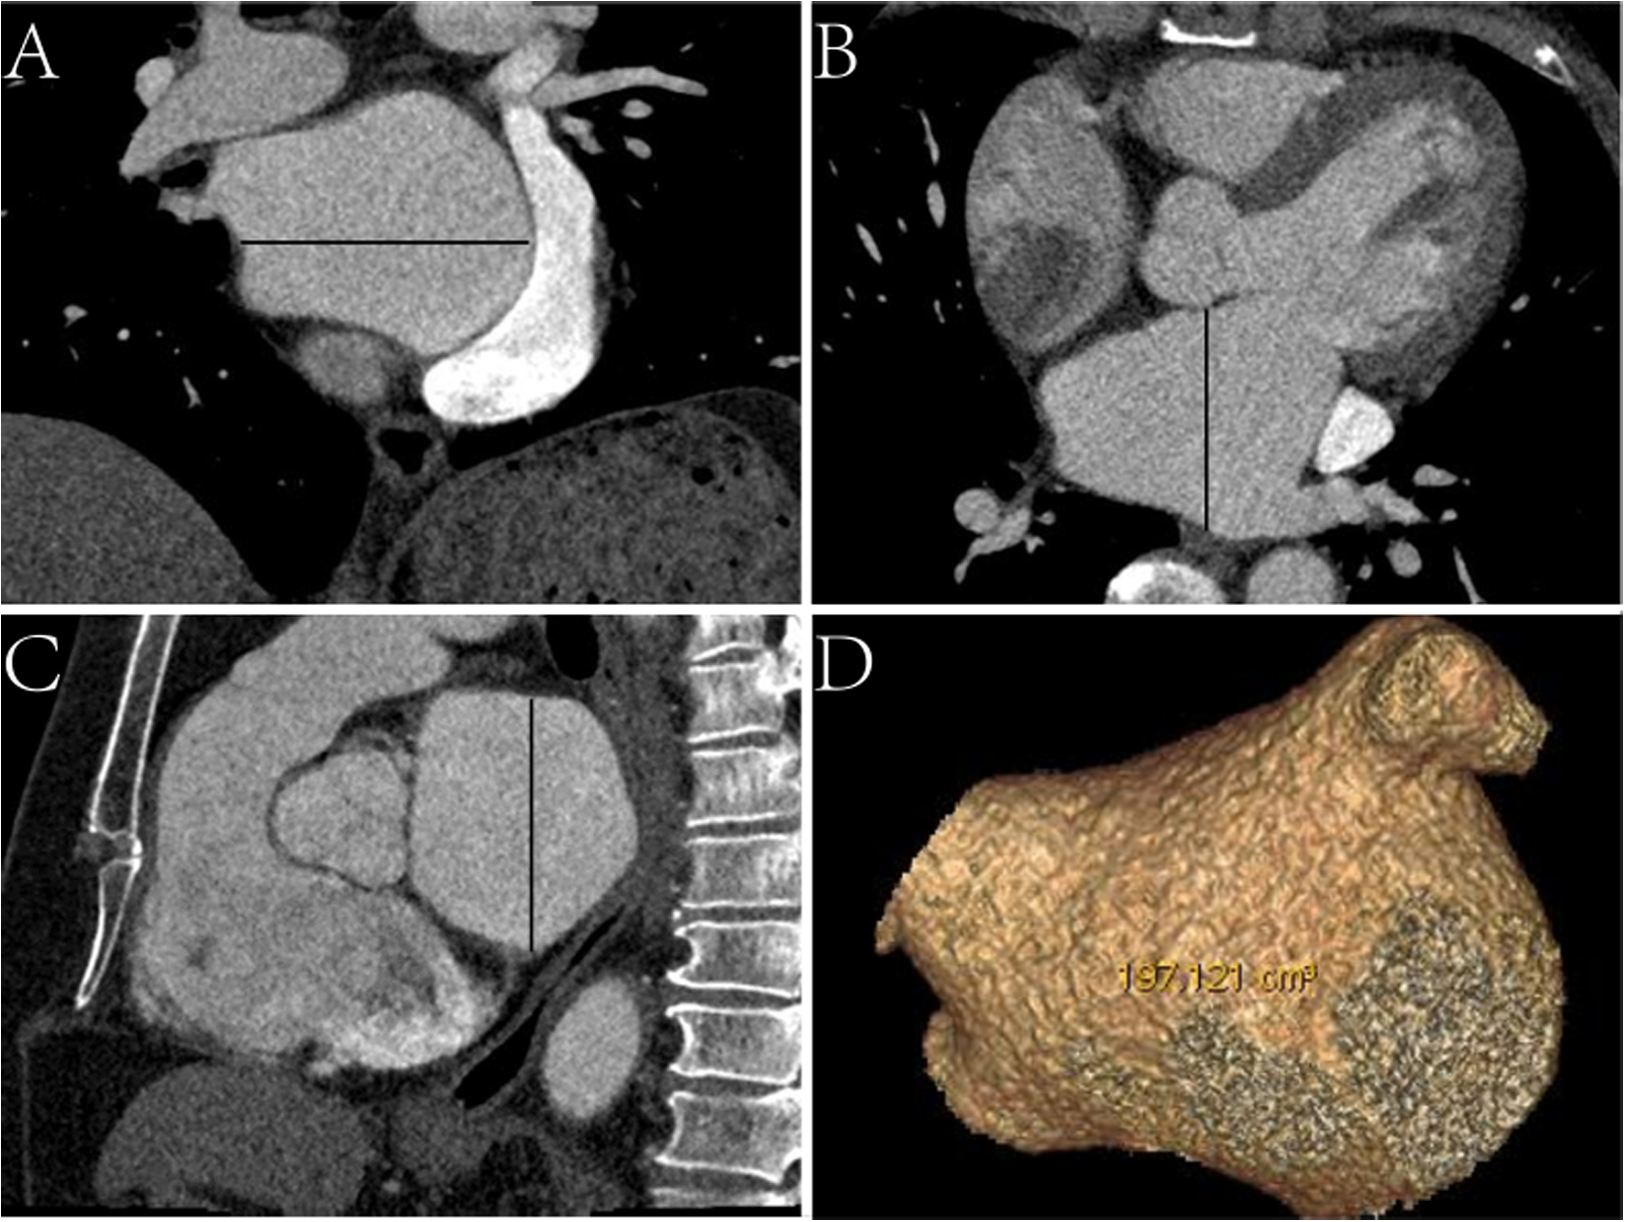

Epidemiological, laboratory, CT, and echocardiographic data were reviewed. CT image data, including left atrial (LA) characteristics (anteroposterior diameter, left–right diameter, upper-down diameter, and volume) (Figure 1) and EAT characteristics (EAT volume and mean density of the whole heart and LA) were assessed. We used the total area of the EAT to calculate the sum of the EAT volume and then separated it into the whole-heart and periatrial EAT.

Figure 1

Schematic diagram of measurements of left atrial CT characteristics. (A) Coronal CT image, the black line represents the left–right diameter. (B) Axial CT image, the black line represents the anteroposterior diameter. (C) Sagittal CT image, the black line represents the upper-down diameter. (D) Virtual reality CT image displaying the volume.